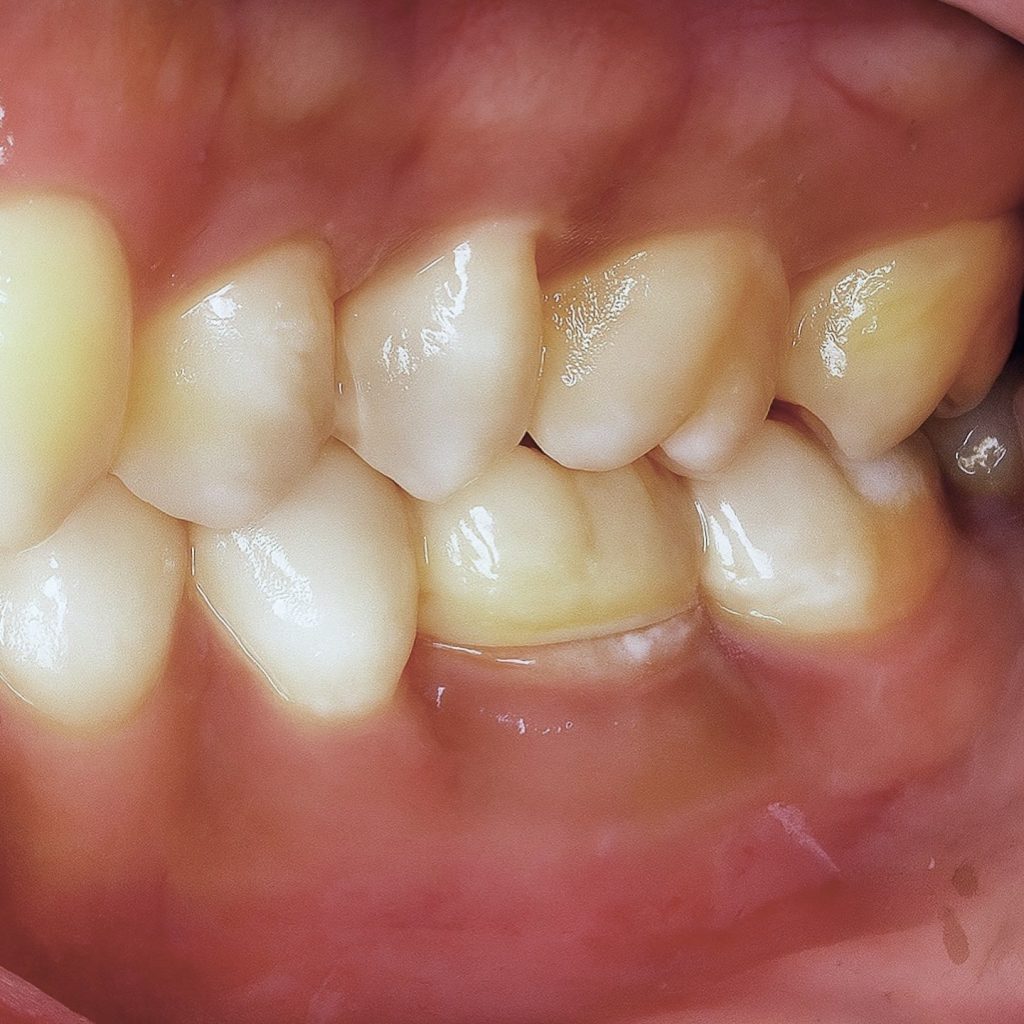

Follow-Up – 1 Year

- Radiographic healing observed – periapical lesion resolved.

- Surrounding bone density improved.

- Soft tissue response healthy and stable.

- Patient asymptomatic, full function restored.

- Restoration clinically intact with excellent marginal integrity.

This case underscores the significance of disinfection, coronal seal, and adhesive principles in the long-term success of endodontic retreatment. Use of Deep Margin Elevation avoided unnecessary crown lengthening or surgical intervention, maintaining tissue health. Immediate post-endodontic build-up reduced contamination risk, while zirconia ensured strength under high occlusal forces typical of mandibular molars.